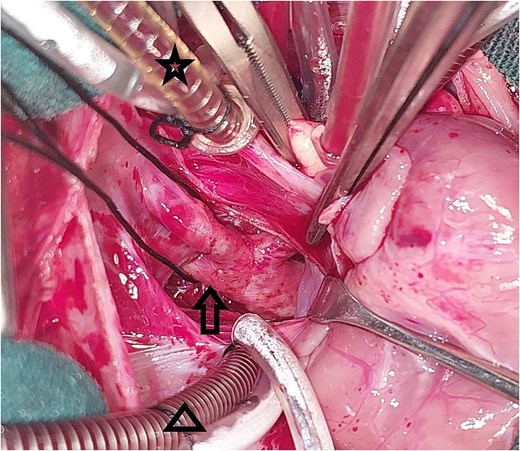

A 20-day-old boy with an unremarkable perinatal history was referred to the pediatric emergency department with respiratory distress. The physical examination revealed poor general condition and central cyanosis. The pulses were bounding in both brachial arteries but the femoral arteries were not palpable. A systolic murmur grade 4/6 was heard along the left sternal edge. The liver was enlarged 2 cm below the costal margin. Transthoracic echocardiography (TTE) was performed and revealed infracardiac TAPVC with associated CoA. Computed tomography angiography (CTA) confirmed the diagnosis of CoA (Fig. 1), and for technical issues, the pathway of CPC was not apparent on CTA. TTE was repeated and the drainage of the CPC into the portal vein was confirmed. The heart team at our hospital decided for urgent surgical repair. At first, the repair of CoA was performed through left thoracotomy with patch plasty technique since the stenosis was too long, and it was not possible to perform resection and end-to-end anastomosis. Then, through median sternotomy, the pericardium was opened, and a total cardiopulmonary bypass (CPB) was prepared. The heart was arrested with an antegrade cold blood cardioplegic solution. The CPC was seen behind the pericardium (Fig. 2). The VV was descending crossing the diaphragm, and it was dissected and controlled (Fig. 3). The heart was lifted out of the pericardium and a long incision was made in LA, and a parallel incision was made in the CPC (Fig. 4). A wide anastomosis was performed between these two incisions thus connecting the CPC into LA. The VV was permanently closed. RA was opened, and a small ASD was closed. The remainder of the operation was completed uneventfully. The patient was weaned off the CPB with stable hemodynamic conditions on low-dose inotropes (milrinone, epinephrin). Postoperative TTE showed normal pulmonary venous drainage without any gradient across the anastomosis, and excellent repair of CoA. After 48 hours on mechanical ventilation, the patient was extubated, and discharged from the ICU after 5 days. On one year follow-up, the patient was with normal growth, and in very good general condition without any complaints. TTE during the follow-up period revealed normal flow in the pulmonary veins.

Intraoperative image showing the pulmonary venous confluence behind the heart: The star points to the venous cannula in the superior vena cava, the triangle points to the venous cannula in the inferior vena cava, the arrow points to the pulmonary venous confluence.